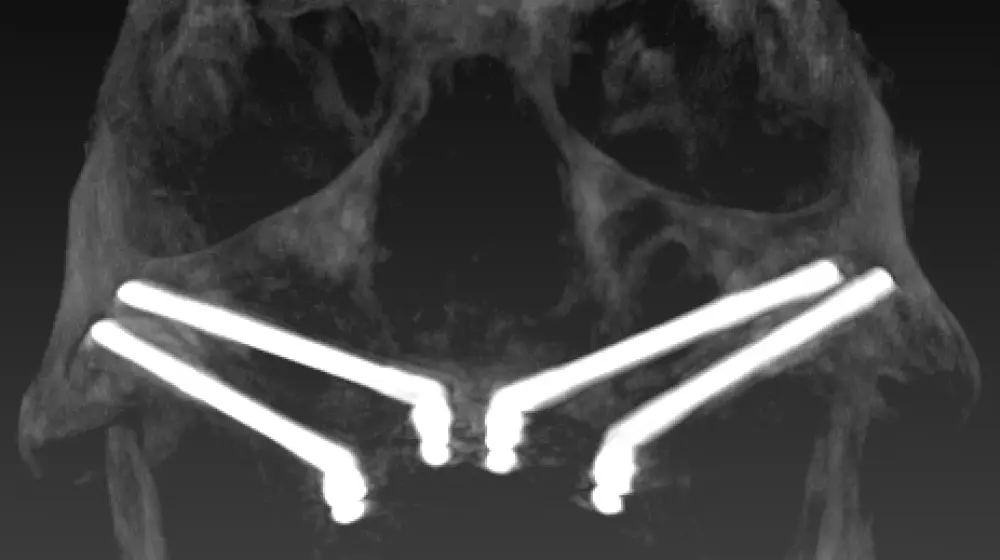

Radiological image illustrating the A-P distribution and positioning of narrow implants in the zygomatic bone following the ZAGA Concept